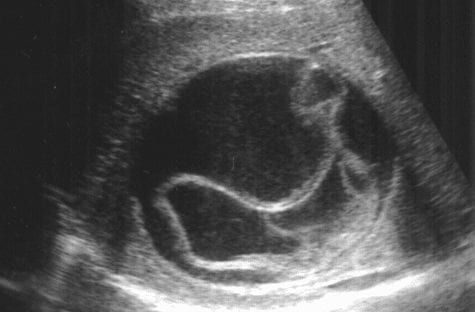

Un uomo californiano, un giorno, ha iniziato a sentire forti dolori addominali e sintomi quali diarrea e vomito. Ad un certo punto ha espulso dal proprio corpo un verme solitario, chiamato tenia, dalla lunghezza di 1,6 metri. Dopo la scoperta si è recato al pronto soccorso portando con sé l’animale all’interno di un sacchetto. I medici rimasero sconvolti davanti all’accaduto.

Il dottor Bahn, ovviamente ci volle vedere chiaro riguardo alla presenza dell’animale all’interno dello stomaco dell’uomo. Così, dopo aver chiesto all’insolito paziente quale fosse il suo regime alimentare capì che il problema era dovuto ad un consumo eccessivo di sashimi e salmone crudo, alimenti tipici della cultura giapponese. L’uomo li mangiava ogni giorno. Difatti il salmone contiene le larve di Diphyllobothrium che provocano proprio l’infezione da tenia.